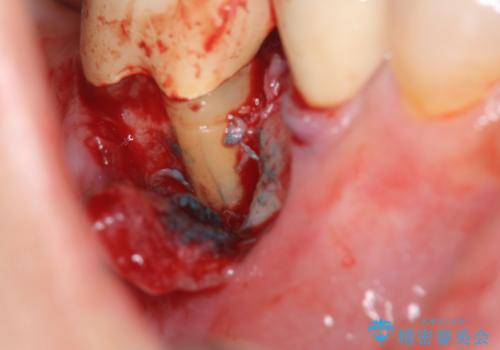

精査した結果、奥歯の根は破折しており抜歯を避けられない状況でした。

咬合力が強く、その他の歯の破折も防ぐために奥歯の咬合機能をインプラントを用いて回復する治療計画を立てます。

歯は大きな力がかかると割れてしまうことがよくあります。

破折した歯はほとんどの場合抜歯が必要になることが多く、インプラントを用いた咬合機能の回復は、また噛めるようになるだけでなく残っているその他の歯を守る意味でも非常に大きな意味を持ちます。